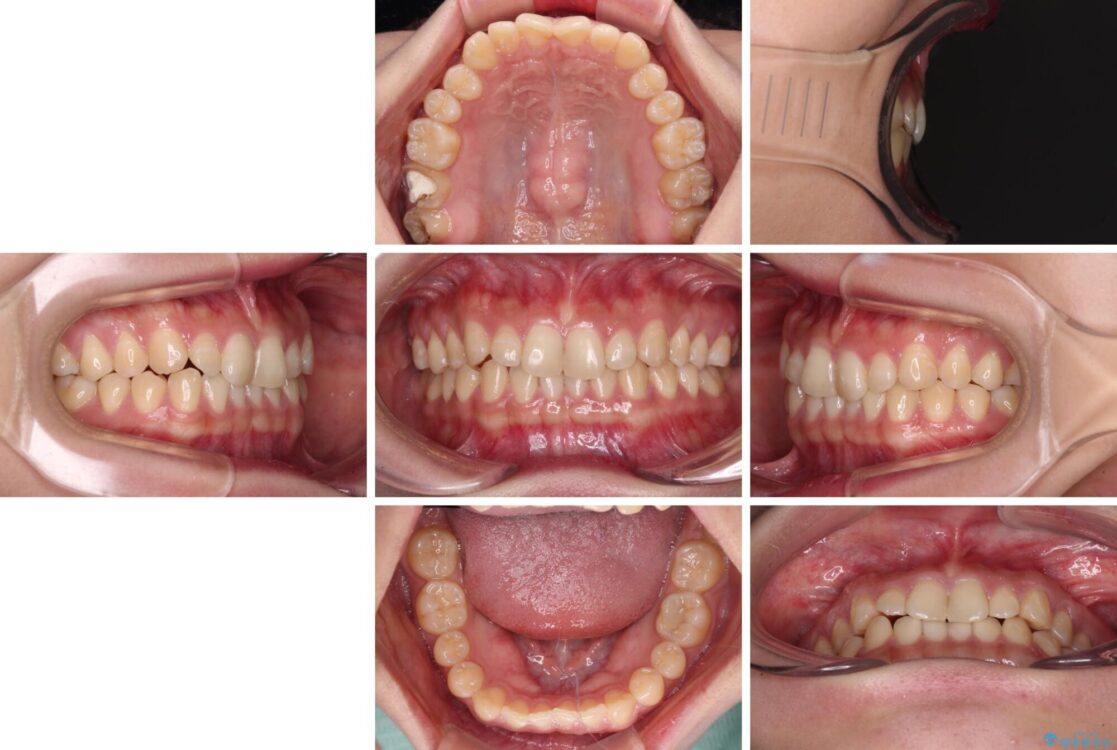

根管治療を行ったままの奥歯と、矯正治療の後戻りを気にして来院された患者様です。

治療前

• 治療途中の奥歯と矯正治療の後戻り インビザライン・ライトによる矯正治療 治療前画像